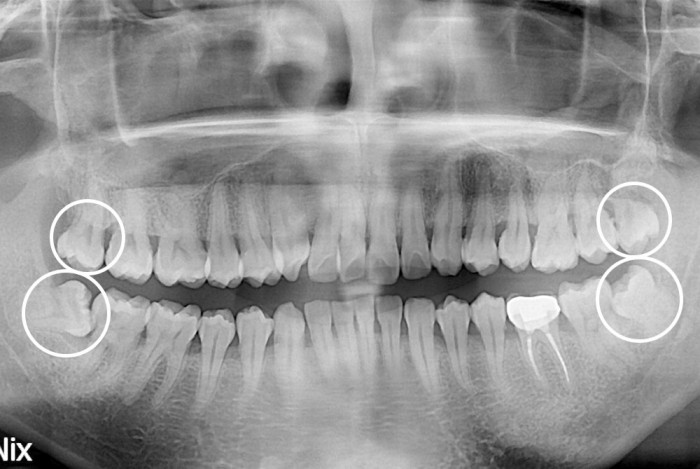

[사랑니] 사랑니

PX20191127_094026_0681_00000000.jpg

치료전 : 2019-11-27